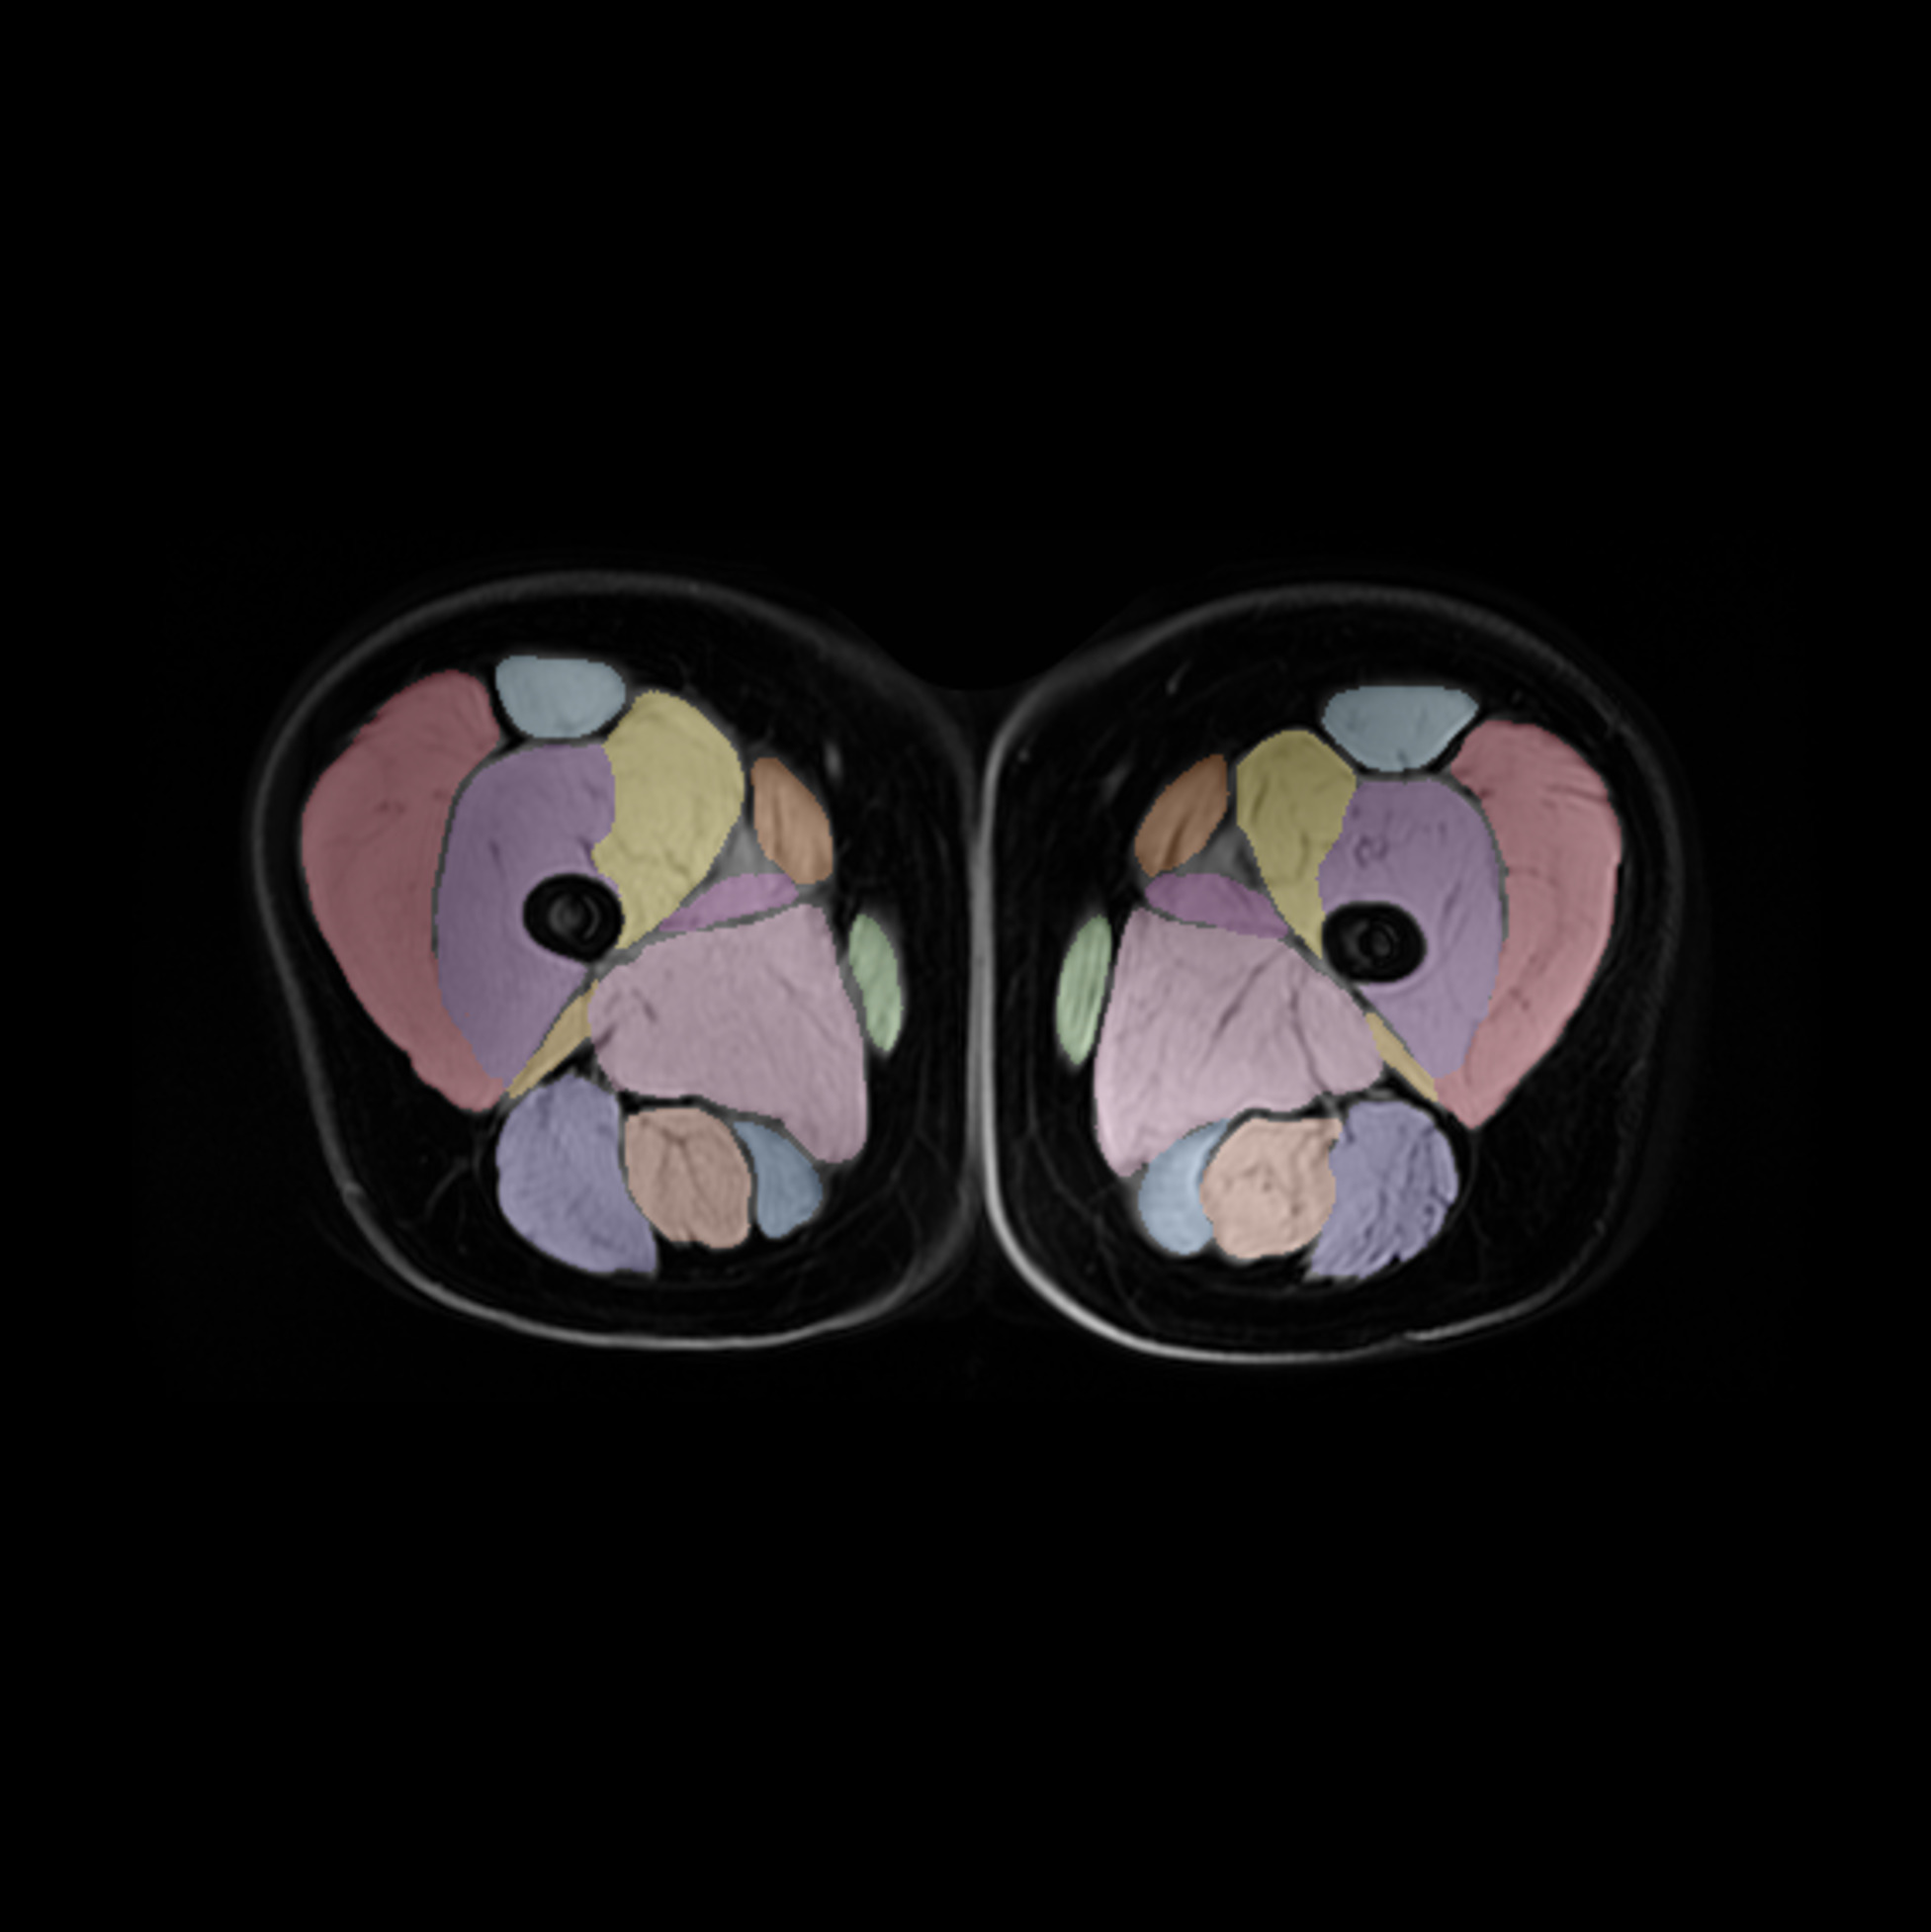

Imaging insights for body composition, muscle changes, and other end-organ effects to be discussed at GLP-1-Based Therapeutics Summit

Ground-breaking imaging for drug development is at the heart of what we do. Equally important is our extensive expertise in drug development and disease biology. This important mix of capabilities allows us to discuss and advise on study-design and to deliver clinical imaging studies addressing relevant biology.